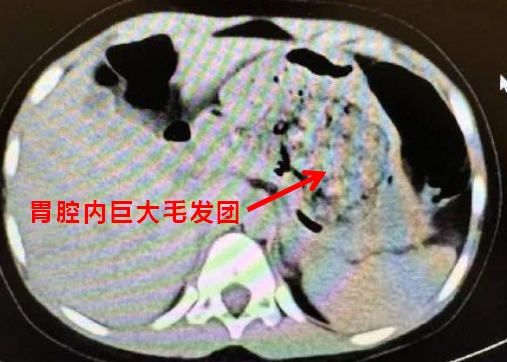

醫(yī)生聽到這里豁然開朗,原來在CT閱片的時候,發(fā)現(xiàn)了孩子胃里面有一團(tuán)密度較高的團(tuán)塊,結(jié)合母親提供的病史,醫(yī)生斷定孩子長期吃頭發(fā)導(dǎo)致了胃內(nèi)毛發(fā)成團(tuán),這也是這次腹痛的原因。

胃里巨大的毛發(fā)團(tuán)

得出了初步診斷后,醫(yī)生立即安排孩子住院,聯(lián)系消化內(nèi)科醫(yī)生做胃鏡檢查,如果能夠明確診斷,可以先嘗試胃鏡下取出,達(dá)到“無創(chuàng)”的效果。結(jié)果,當(dāng)胃鏡進(jìn)入的瞬間,所有人都驚呆了,孩子胃內(nèi)的毛發(fā)包裹食物殘渣形成了一個巨大的團(tuán)塊,充滿整個胃腔。